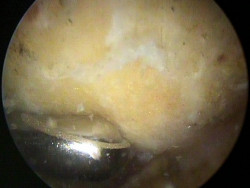

Das Bild links zeigt den nach unter ragenden Knochensporn, das Bild rechts zeigt die unter dem Knochensporn aufgeriebene Sehne und ein Operationsinstrument). Dieser Knochensporn wird dann zunächst von den Weichgeweben befreit und mit dann abgetragen, damit die Unterfläche des Schulterdaches dann glatt und eben ist.